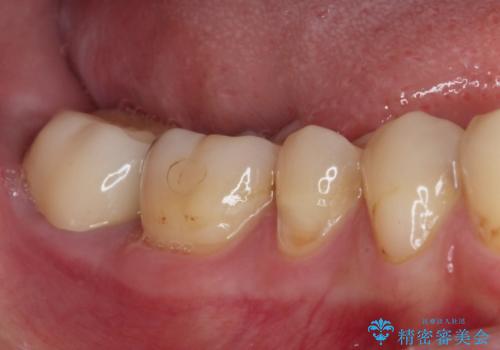

検査の結果、右前歯の歯根が縦に破折していることが分かりました。

以前に装着した保険診療の前歯の外見も気になるとのことで、前歯4歯の治療を行うこととしました。

破折している歯は抜歯をし、歯肉が窪んでしまうので、傷口の治りを待って、歯肉移植を行うこととしました。

1歯は根管治療を行うことが必要と判断されたため、根管治療を実施することとしました。

歯肉移植や根管治療終了後、オールセラミッククラウンおよびブリッジにて補綴することとしました。